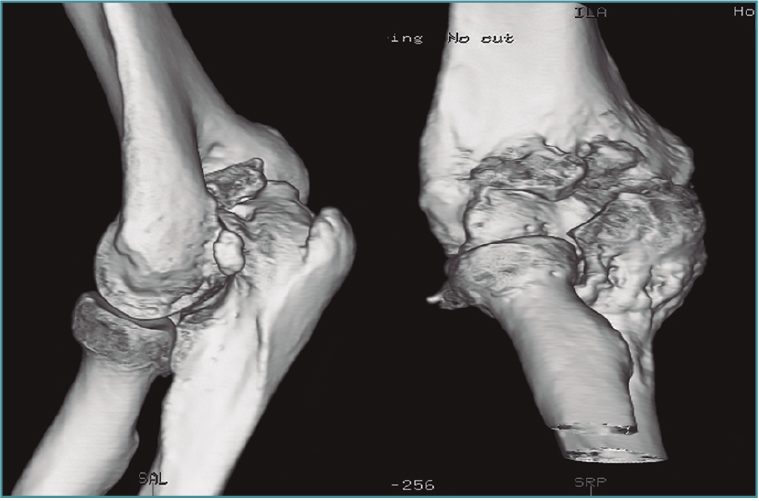

Figura 5. Reconstrucción sagital y tridimensional de una malunión de húmero distal, con alteración de la alineación de la superficie articular en extensión y malrotación interna, que condiciona una pérdida de flexión, como ejemplo de rigidez intrínseca.